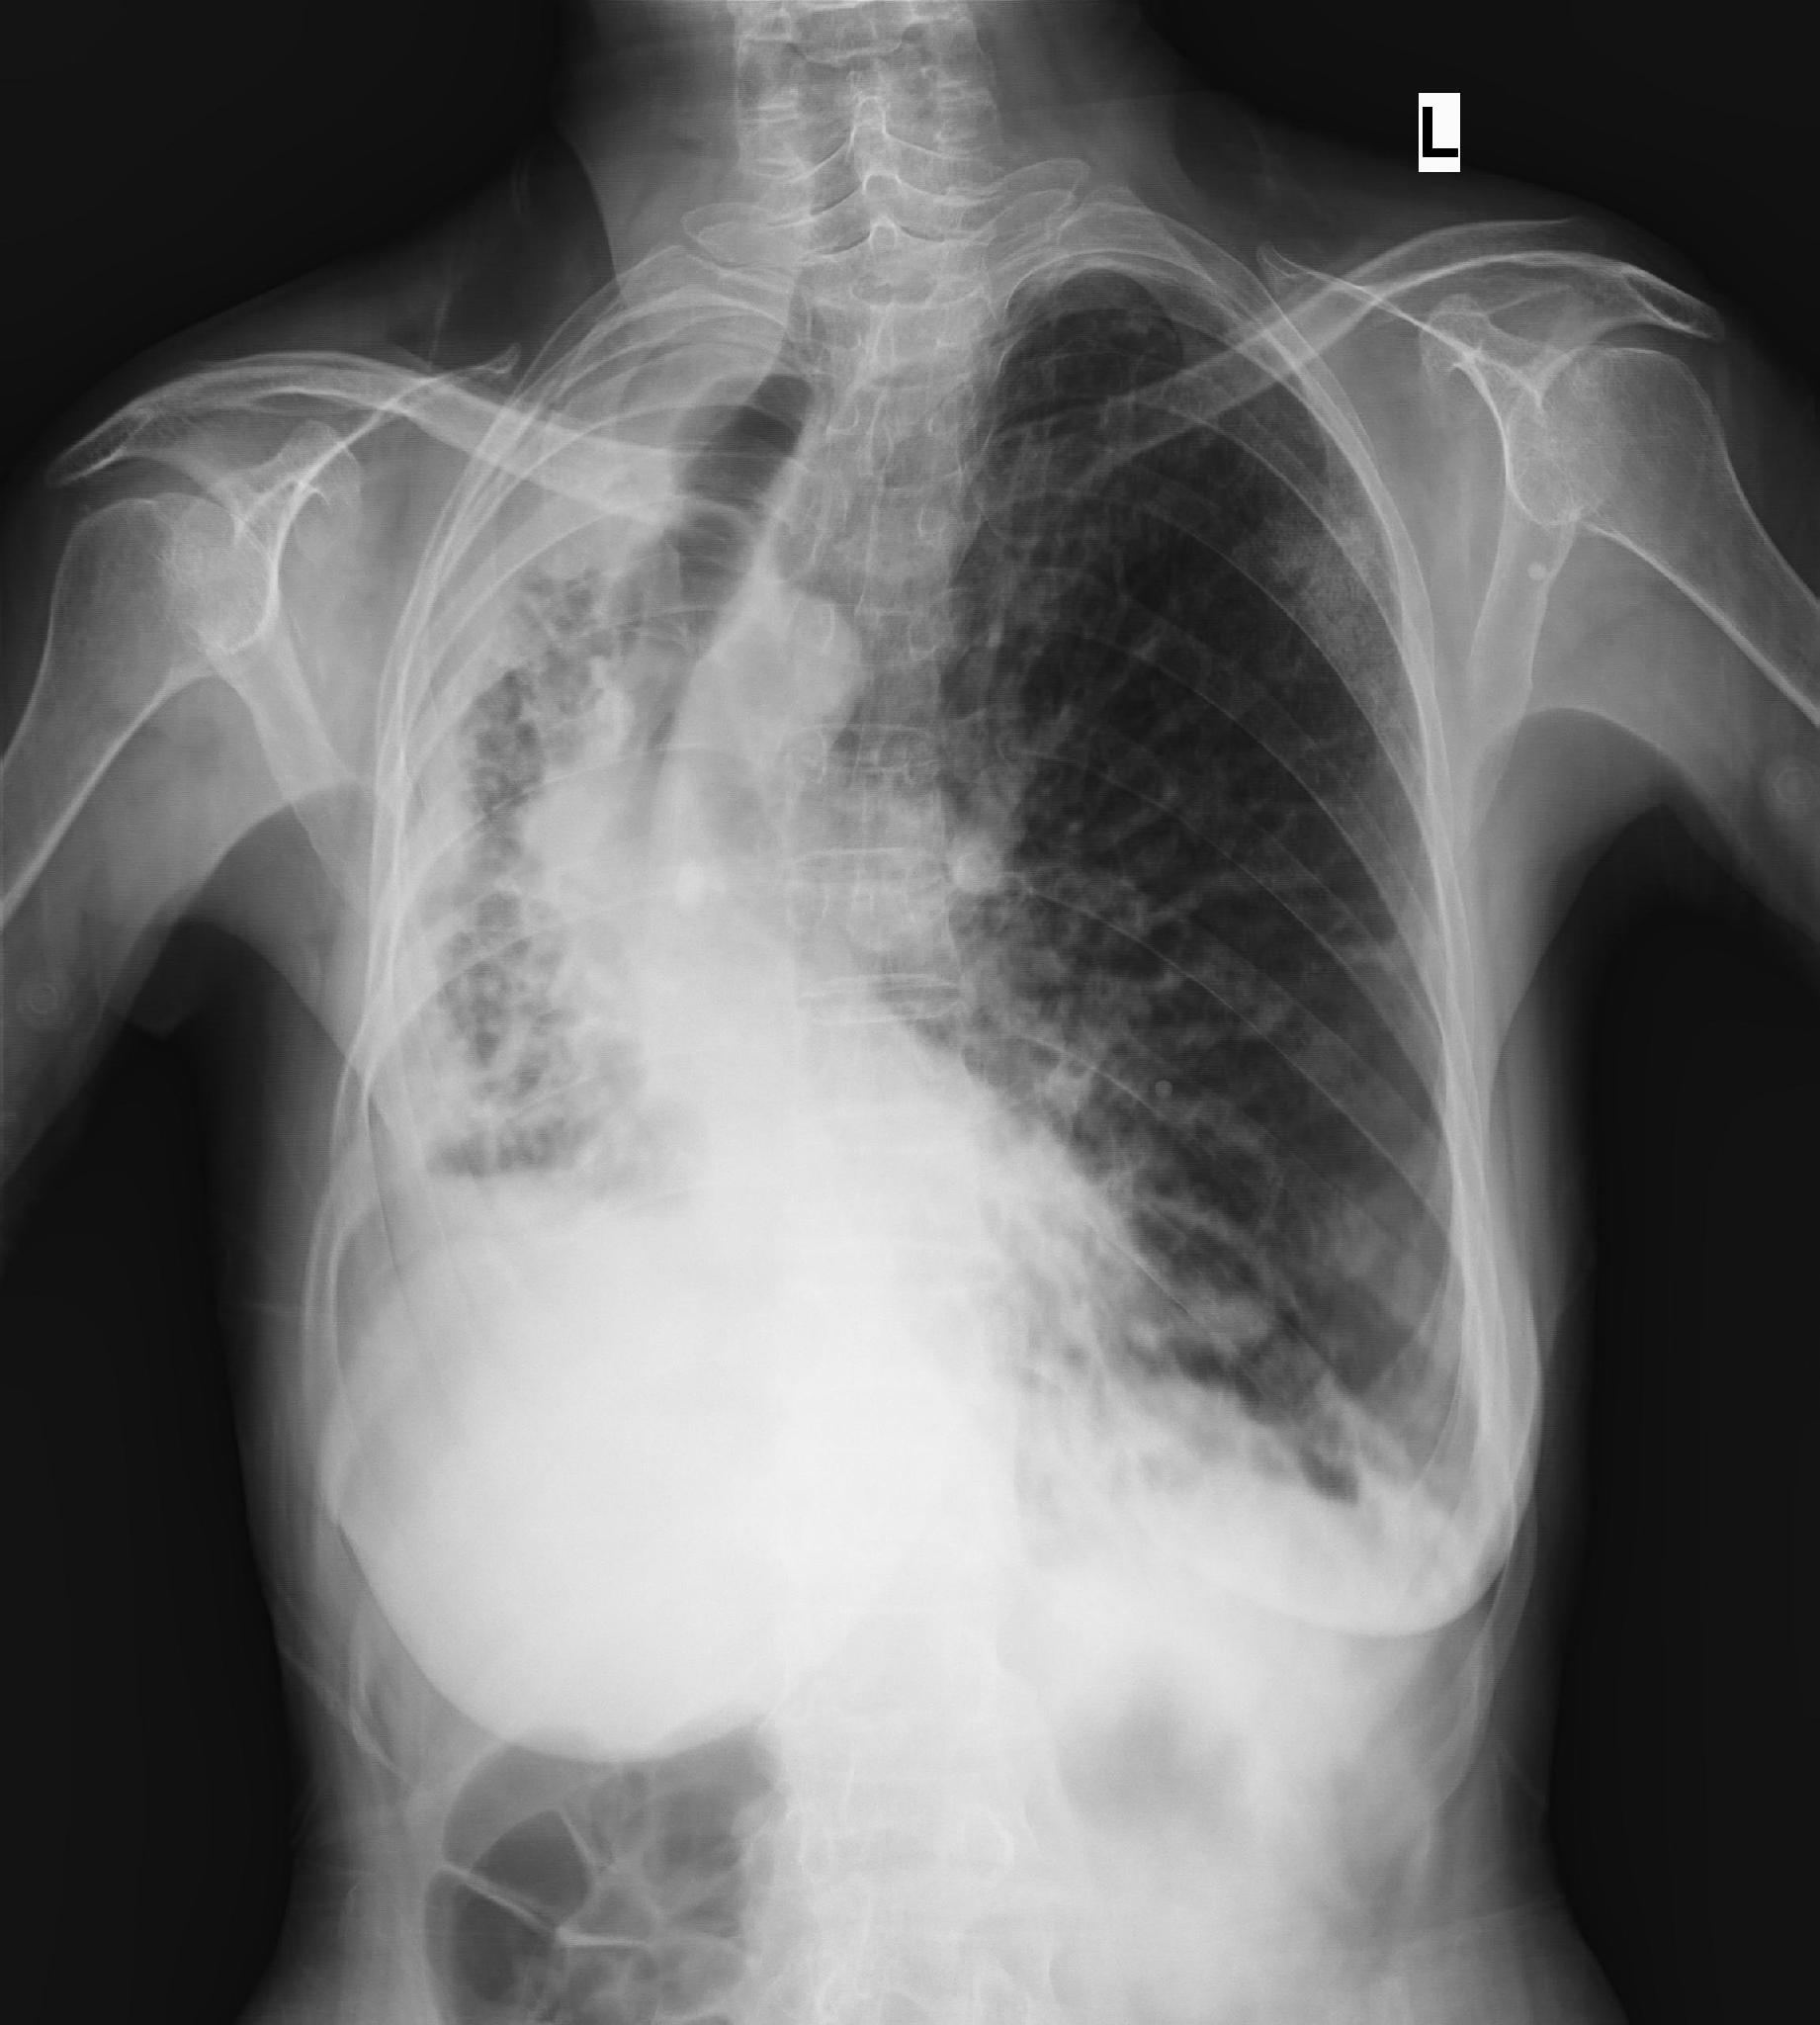

肺纖維化圖片

_左下肺肺纖維化影像